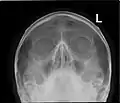

Paranasal sinuses radiograph (occipitofrontal)